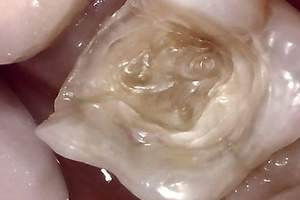

症例① セラミックインレー

治療前

治療後

年齢 60代女性

主訴 歯がしみる

治療方針 つめ物がすでに入っている歯です。そのため、見た目では虫歯があるかどうかわかりませんでしたので、レントゲンを撮影しました。すると、つめ物の中で虫歯になっていることがわかりました。虫歯は、とても大きくなっており神経に近い部分まで進行していました。

治療内容 神経が保存できるかどうか経過をみるために、覆罩といって、神経を守るための処置を行いました。2ヶ月ほど経過を見て、症状が出ないことを確認して、つめ物の型をとり、つめ物をいれていきました。

治療期間 3ヶ月

リスク・副作用 治療後に冷たいものがしみるなどの症状がでることがあります。つめ物を入れた後に痛みなどの症状が出てしまう場合は神経を取り除く治療が必要になります。

費用 ・セラミックインレー:55,000円(税込)

見た目では全くわかりませんが、レントゲンでは黒く抜けて虫歯になっていることがわかります。

虫歯の見分け方

治療中

治療中①

治療中②

治療中①:つめ物をとったところ。茶色い部分は虫歯になっている。

治療中②:染色液を用いて虫歯を選択的に取り除いた。歯はかなりなくなっており、神経近くまで進行していた。

経過観察

虫歯を取り除いた後、神経を守るためのお薬をつめて、2ヶ月ほど経過観察をした。

経過観察中に症状がでなかったため、セラミックのつめ物をいれていった。